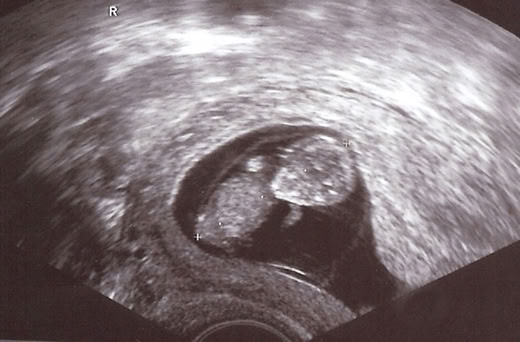

Kinderwunschbehandlung mit Hypnose

Sie wünschen sich Kinder, es will aber einfach nicht klappen, obwohl körperlich alles in Ordnung ist? Dafür kann es eine ganze Reihe von Erklärungen geben. Psychische Dinge spielen oft eine sehr wichtige Rolle, auch wenn die Betroffenen sich darüber selten bewusst sind.

Je mehr und länger es das Paar versucht, je mehr man probiert, desto größer wird im Laufe der Jahre der Kinderwunsch und die Anstrengung, ein Kind zu bekommen. Daraus entsteht dann schnell solch ein großer Druck, dass allein dieser psychische Druck ausreicht, um eine Schwangerschaft zu verhindern. Die Zusammenhänge sind sehr komplex und man würde den einzelnen Betroffenen nicht gerecht, wollte man zu sehr vereinfachen. Aber wie oft kann man zum Beispiel erleben, dass ein Paar schließlich ein Kind adoptiert und schon nach kurzer Zeit wird die Frau doch noch schwanger! Es ist, als hätte die Adoption oder allein die Entscheidung dazu all den Druck von Jahren genommen und schon nimmt die Natur von selbst den gewünschten Verlauf. Was auch immer seelisch/psychische Ursachen sein mögen, die Methoden der klinischen Hypnose (Hypnotherapie) mit generativen Trancen und Selbsthypnose haben sich auch in solchen Fällen sehr bewährt. Hypnotherapie ist eine der wirkungsvollsten Methoden, Stress abzubauen und die kreativen inneren Kräfte in Richtung der gewünschten Ziele zu aktivieren.